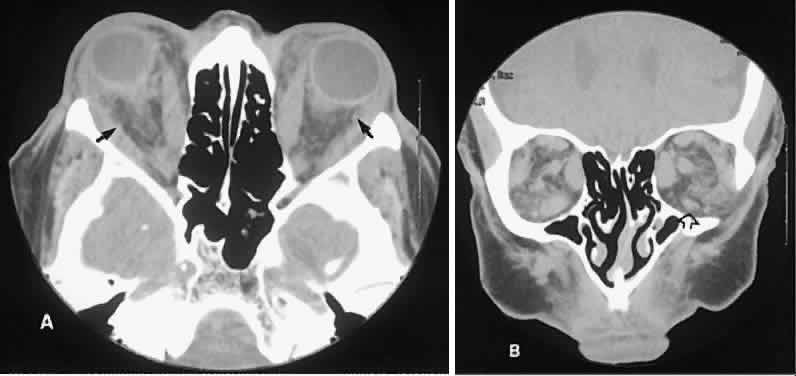

The superior ophthalmic vein (SOV) is an important vascular structure to recognize. It begins in the superior nasal quadrant near the trochlea before coursing posteriorly and laterally beneath the superior rectus muscle, exiting the orbit through the superior orbital fissure. Drainage is into the cavernous sinus. Asymmetric enlargement, especially in the presence of an ipsilateral cavernous sinus enlargement, suggests a vascular anomaly, which may require selective carotid angiography for further definition. Enlargement of one or multiple EOMs in this setting is likely. The SOV also may be enlarged as a result of any process impeding drainage from the orbital apex, such as dysthyroid orbitopathy or metastatic disease.

The optic nerve occupies the central intraconal space. By necessity, the nerve has a certain amount of slack, which is necessary to permit movement of the globe. In the axial plane, the optic nerve has an undulating course and thus may appear thicker or thinner as a result of partial volume averaging as it passes in and out of the axial plane. It is imperative to recognize this normal pattern for proper interpretation of axial images.

The optic nerve itself is invested by the same meningeal layers that cover the brain, and the intracranial space may extend along the course of the optic nerve to the back of the globe. Enlargement of this space may be recognized as pseudomeningoceles of the optic nerve sheath. It is sometimes possible to tell whether the nerve, the sheath, or both are enlarged by CT scanning, although MRI affords the better view.